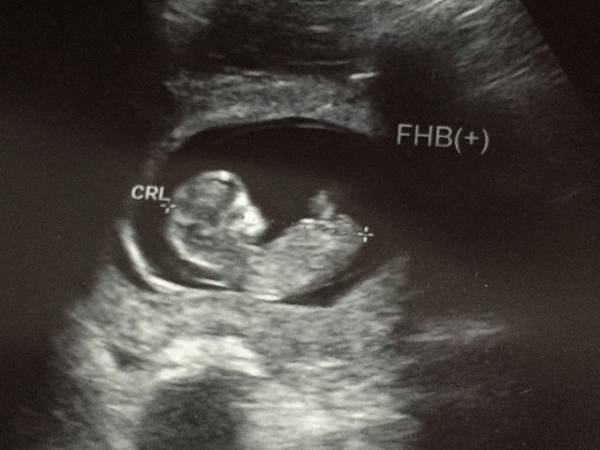

小小的胚胎,超可愛的吧 > //// <

〖23 w〗脹氣、便秘、腸胃絞痛... 醫生建議我每天要喝足2,000 cc的水分。高層次超音波,確定寶寶性別,第一次看到4D的寶寶長相。想出第二個 中文 ideal baby name

寶寶很喜歡在媽咪肚子裡玩臍帶、喜歡用小手手遮住自己的臉(不喜歡看鏡頭)> //// <

當時我還問了超音波師:「是不是太亮了?」所以寶寶都不正面對我們,哈哈哈XDDD

( 醫師說媽咪的腹中是非常暗的喔,所以其實寶寶也看不到東西)

只能說小小的他很有自己的個性吧 ![]()

看到很多在寶寶周圍的小水泡,那就是氧水 感覺好可愛喔 <有點像是「不存在的世界」>